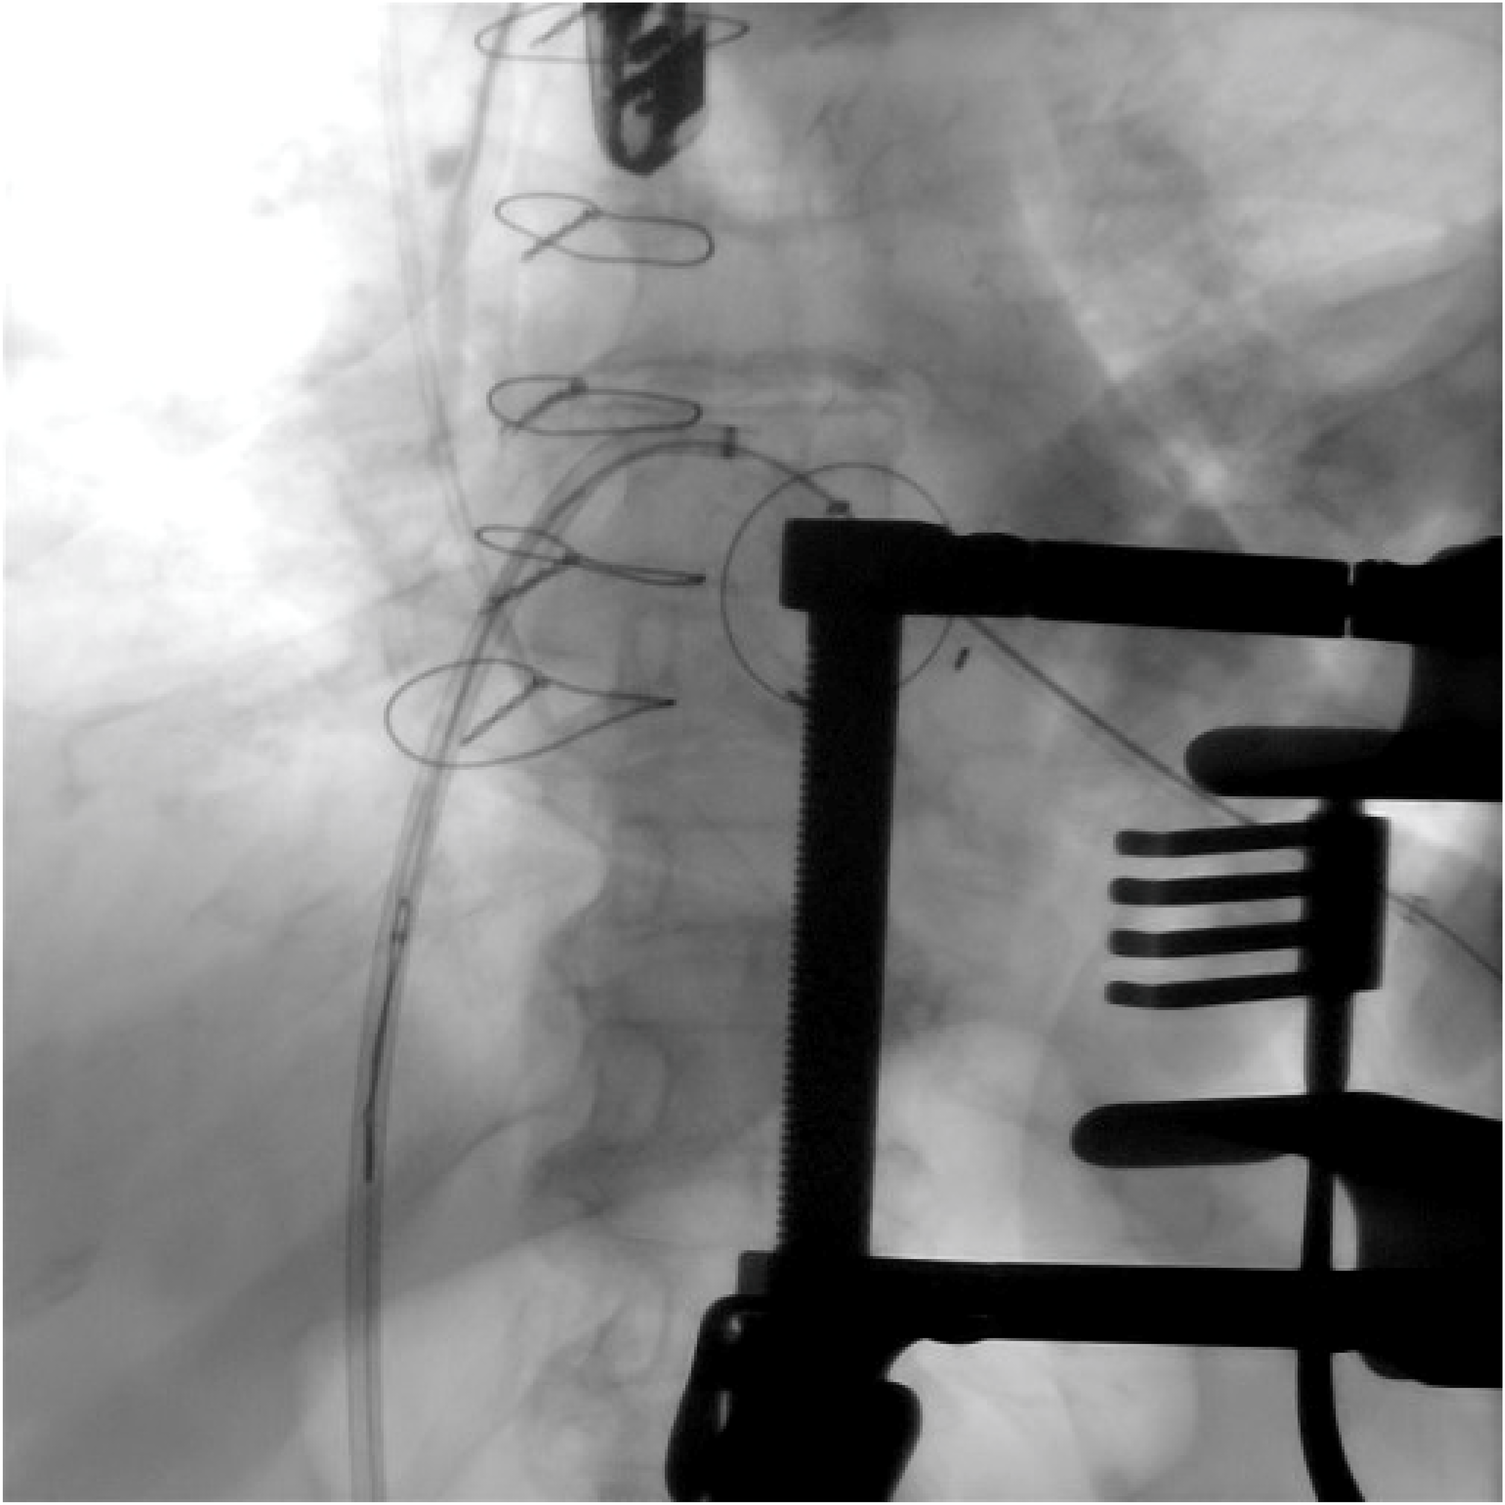

Figure 4

The snaring via the transseptal catheter of a soft-tipped guidewire introduced through a small-gauge apical needle into the LV cavity, passed across the degenerated mitral prosthesis into the left atrium.